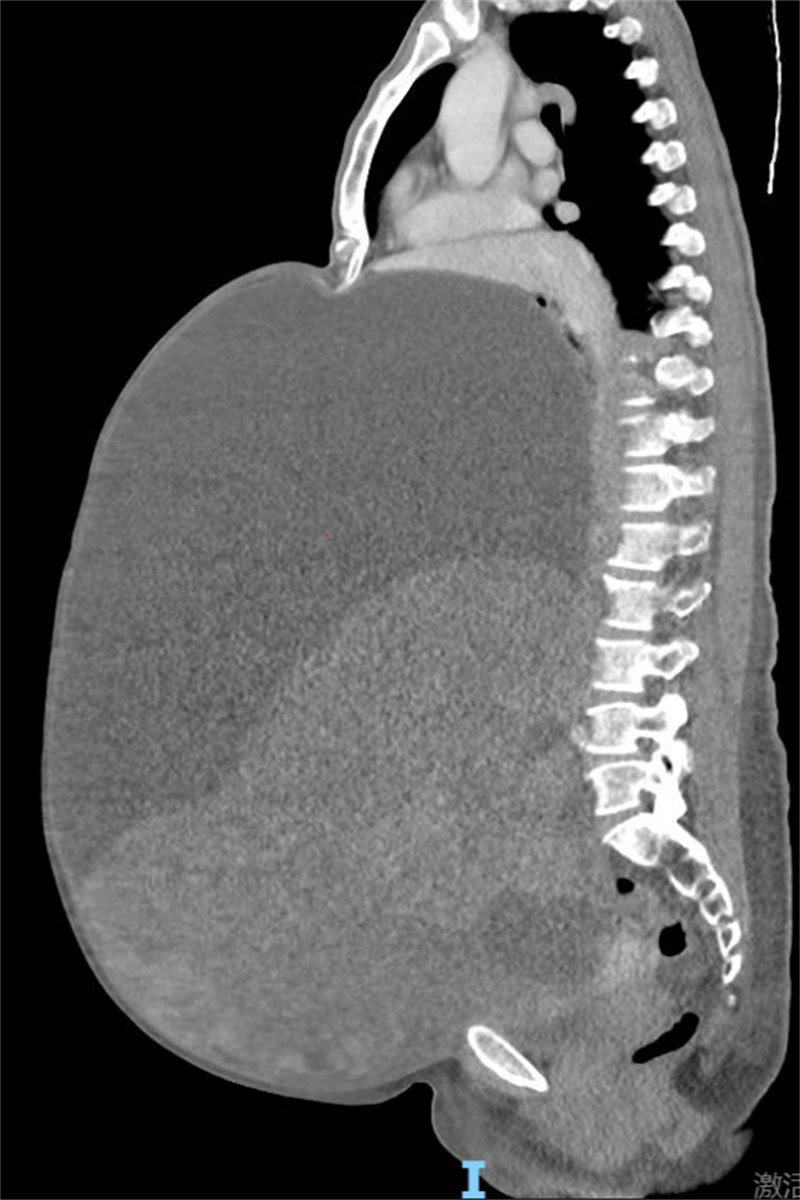

原來,林阿姨腹部脹大已有近3年,一直以為是身體長胖沒在意。直到最近出現(xiàn)呼吸困難、無法平臥等癥狀,她才想到就醫(yī)。先后兩次在外院檢查時(shí),腹部CT均顯示腫瘤已填滿整個(gè)盆腹腔,不僅壓迫腸管、輸尿管及大血管,還把心肺擠得向上移位,子宮更是被壓成“薄片”。

面對(duì)這一棘手病例,柳州市人民醫(yī)院婦科團(tuán)隊(duì)立即將林阿姨收治入院,并迅速組織麻醉科、普通外科等科室專家開展多學(xué)科聯(lián)合診療。腹部CT進(jìn)一步明確:腹盆腔巨大囊實(shí)性腫塊,傾向附件來源惡性上皮源性腫瘤,不排除黏液性囊腺癌可能。